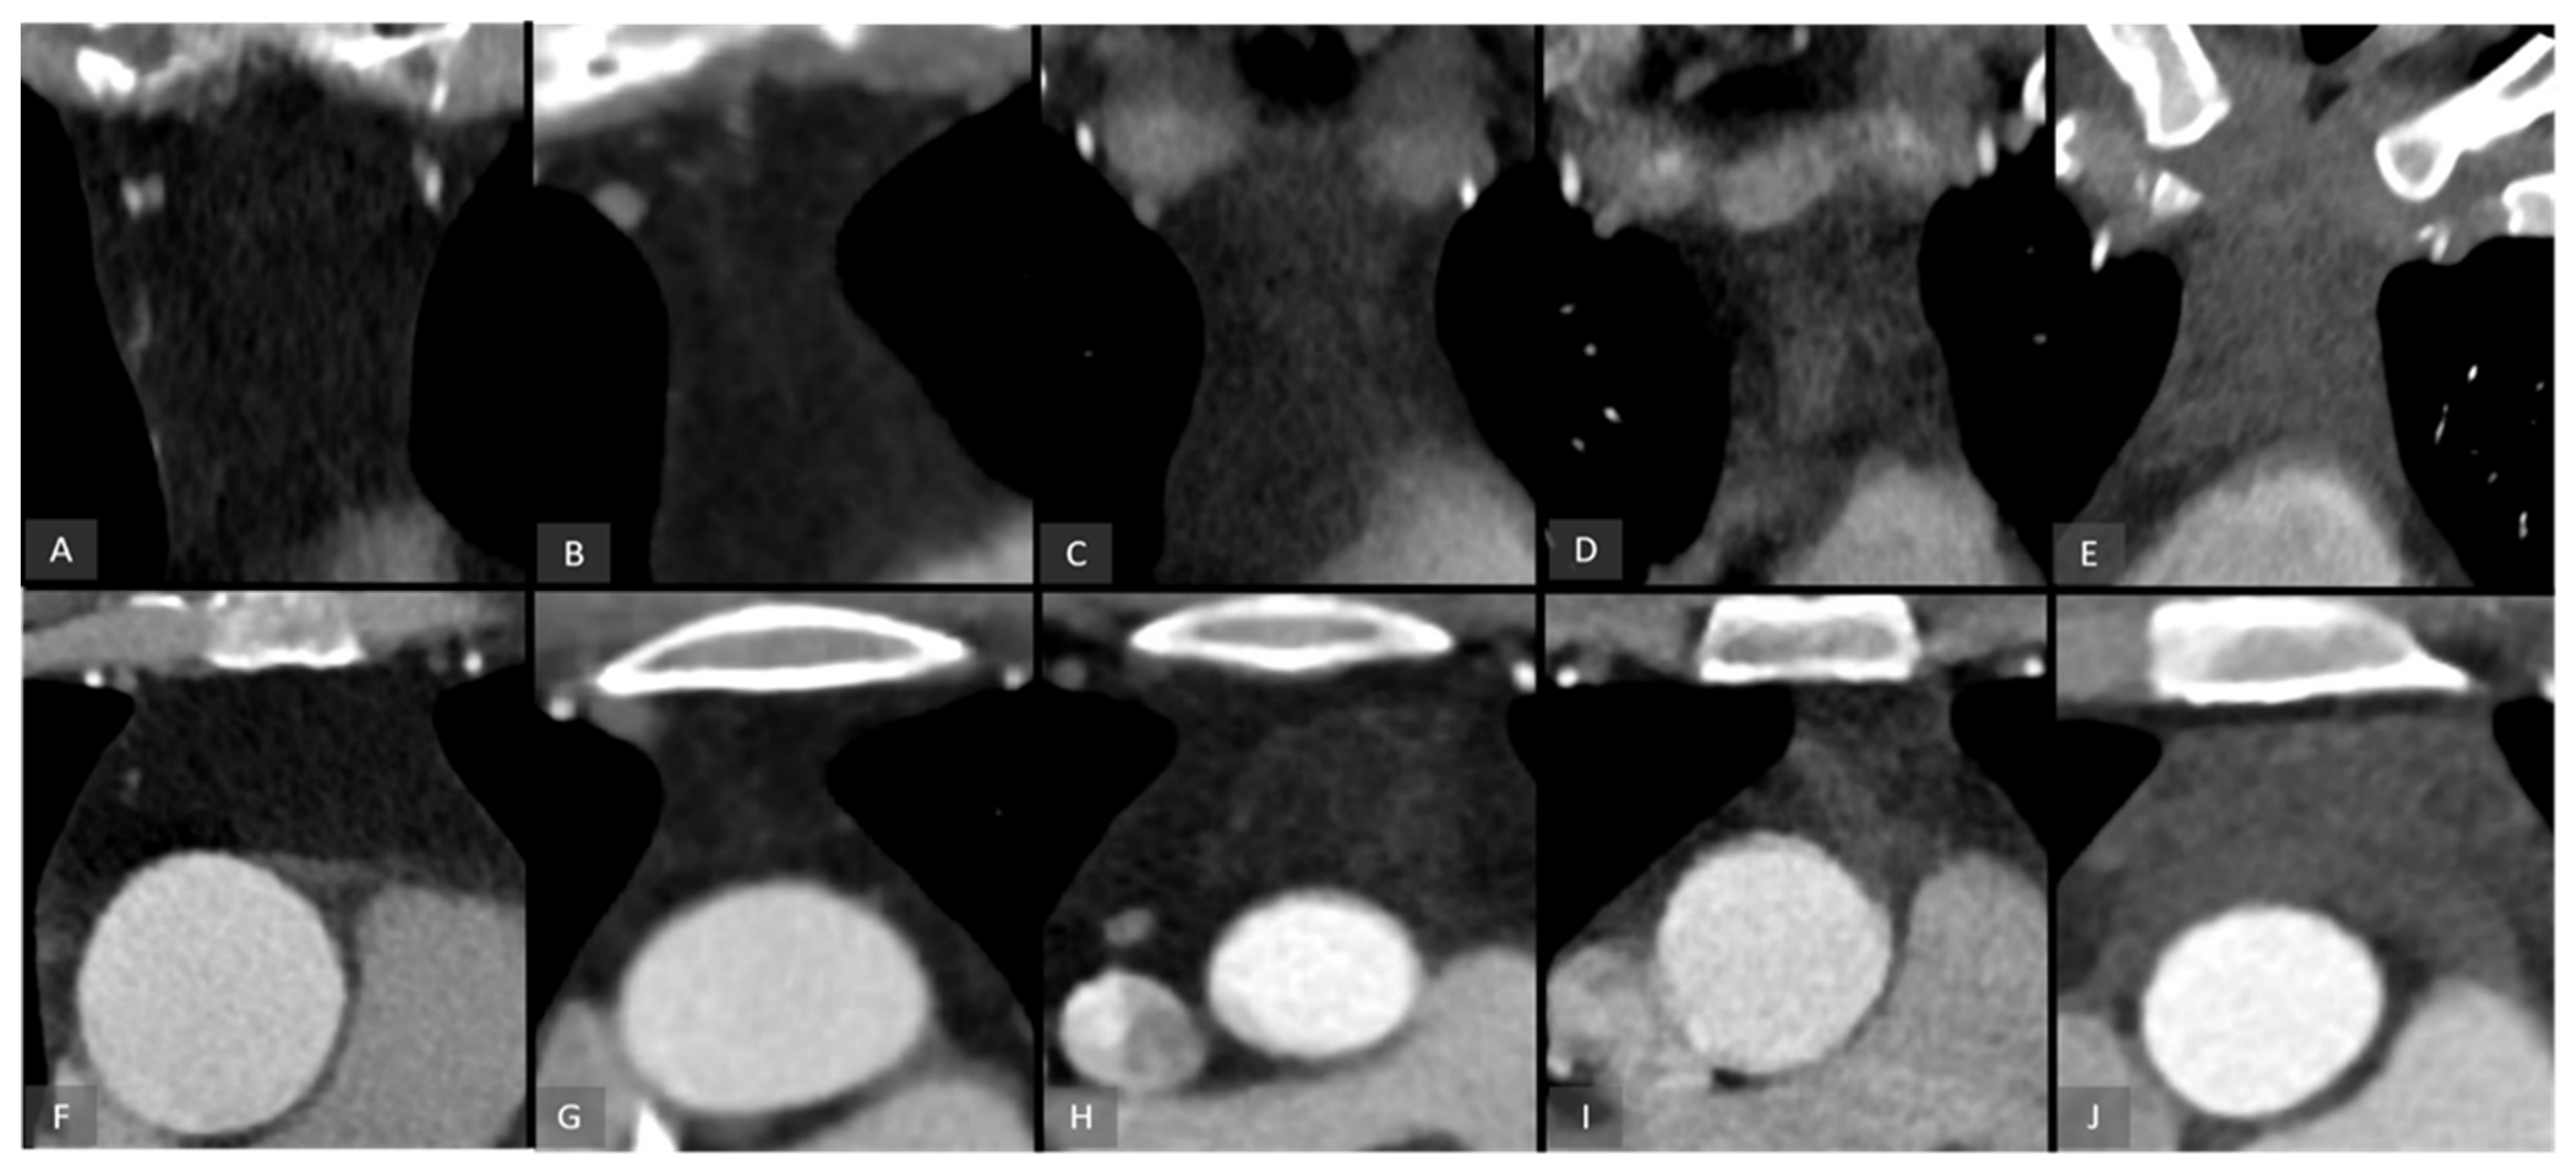

2.4. Image Grading of the Thymic Tissue

- Grade 0: Complete fatty replacement of the thymus;

- Grade 1: Predominantly fatty tissue with minimal residual thymic components (<25%);

- Grade 2: Mixture of residual thymic tissue and fatty tissue components (25–50%);

- Grade 3: Residual thymic tissue with minimal fatty tissue components (50–75%);

- Grade 4: Almost complete residual thymic tissue (>75%).